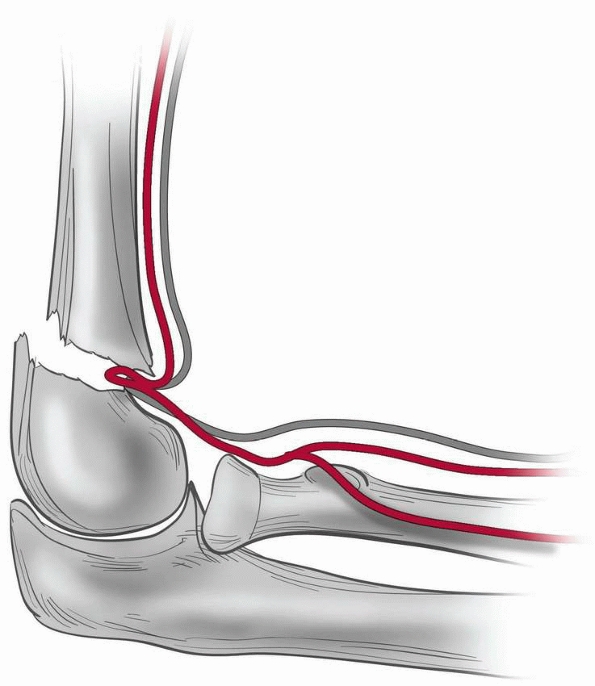

The brachial artery and median nerve may become entrapped in the

fracture site with lateral displacement, but they are highly unlikely

to become entrapped with the distal fragment displaced medially. The

brachial artery is placed further at risk by the ulnar-sided tether of

the supratrochlear artery (Fig. 14-6).171